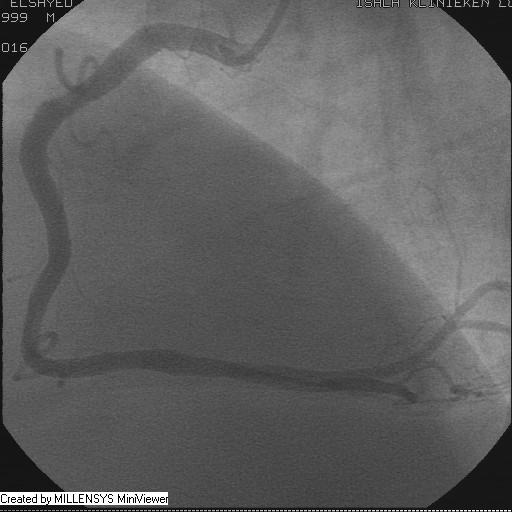

Patient transfered to Cardiac Catheterization Laboratory, coronary angiography showed atherosclerotic coronaries but without significant lesions, especially LAD that was patent with TIMI 3 flow (Figure 1- 5). Re-evaluation of the Angiography showed a small stump that can be for an occluded 1st diagonal (Figure 2a), at that level the LAD has a non-significant lesion.

Figure 2A

Figure 5